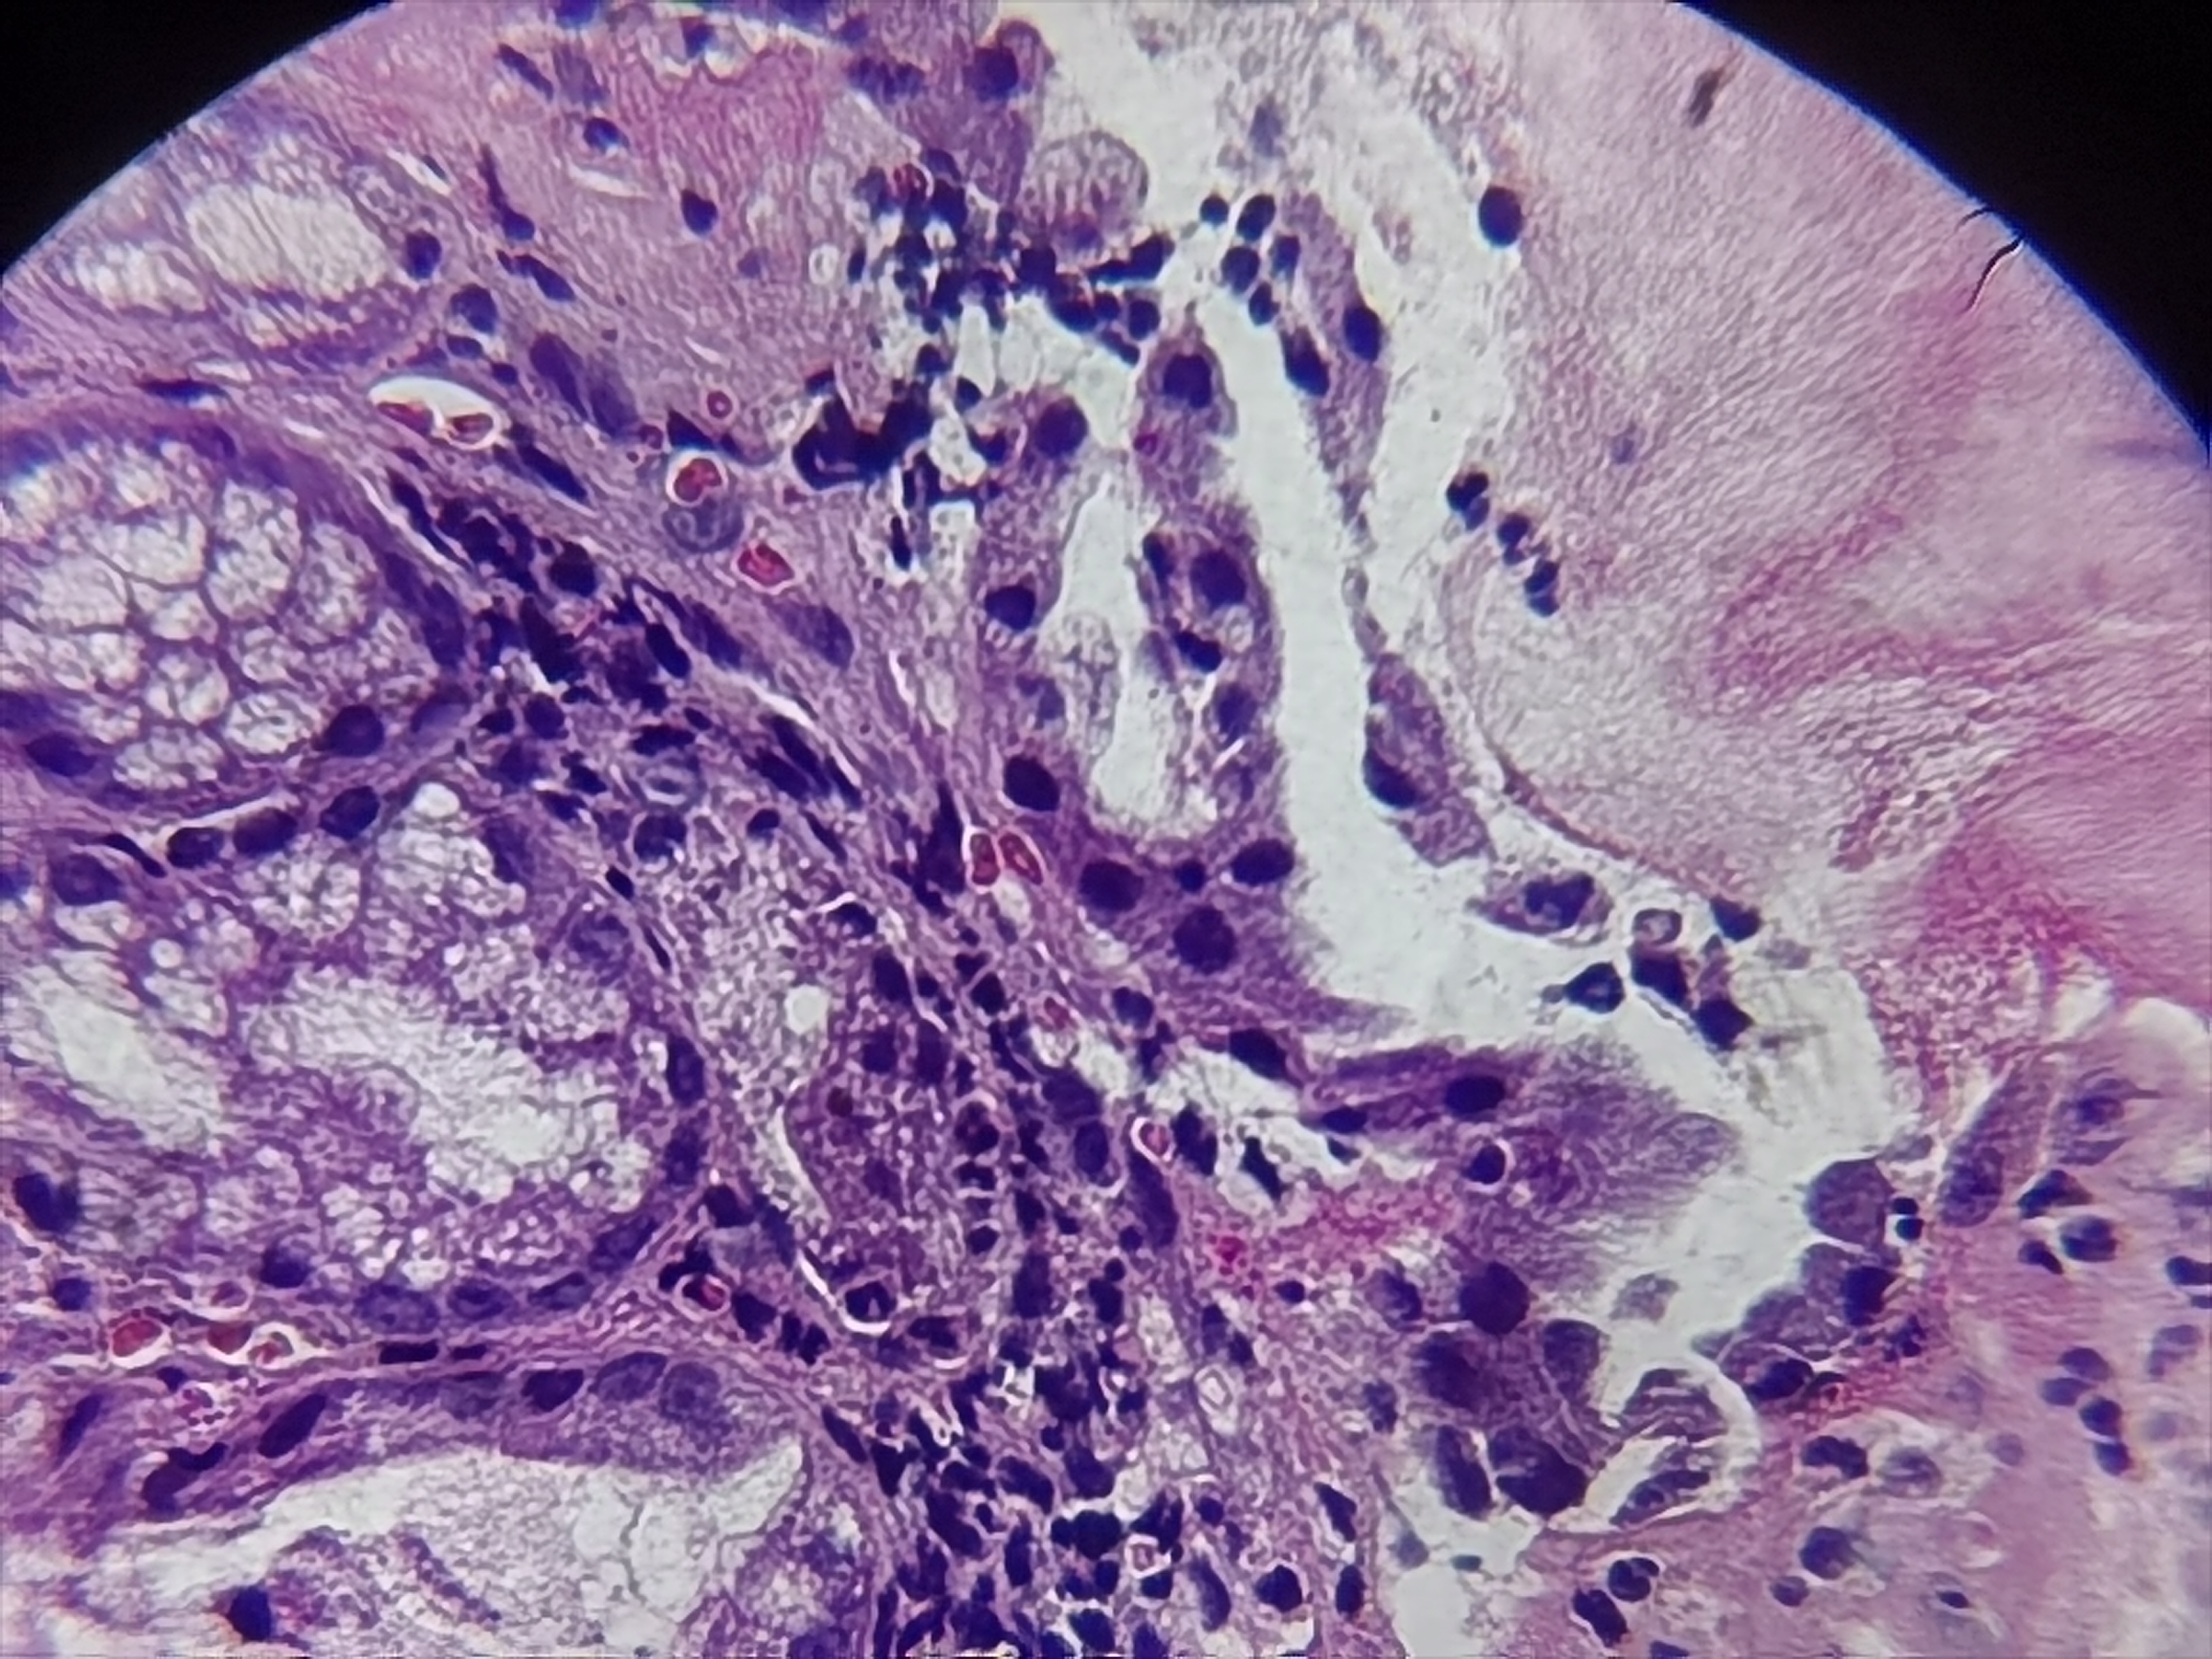

十二指肠球部活检

十二指肠:球部变形,可见溃疡,周围粘膜充血水肿

十二指肠球部粘膜活检

灰白色组织1块

粘膜慢性炎溃疡形成